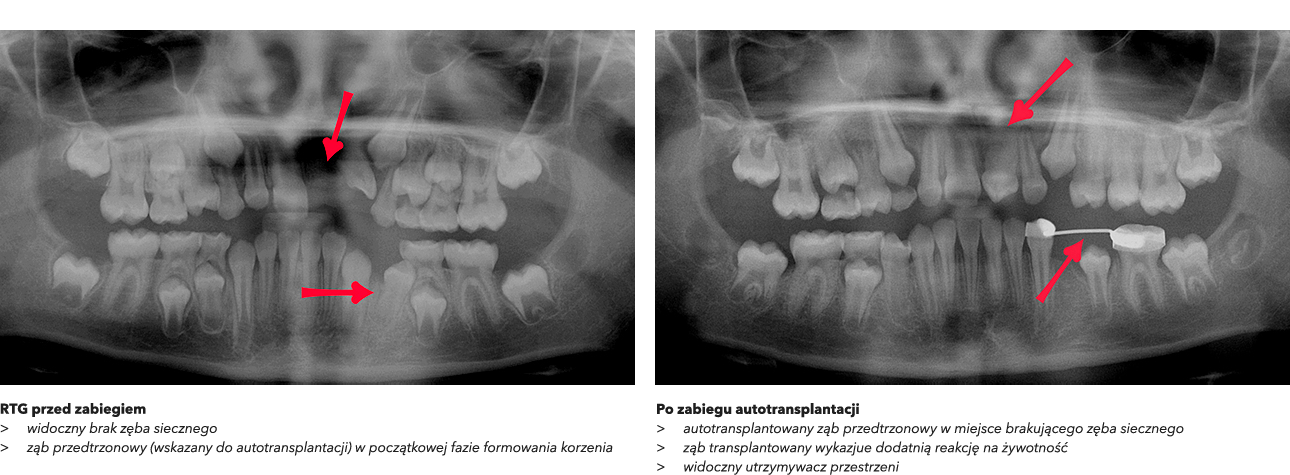

>   Autotransplantacja w miejsce 11 – przeniesienie własnego zęba pacjenta w celu uzupełnienia brakującego zęba w przednim odcinku szczęki.

W przypadku naszej pacjentki celem leczenia było szybkie przywrócenie funkcji narządu żucia oraz trwała odbudowa brakującego zęba w przednim odcinku szczęki. Po analizie dostępnych opcji zdecydowano się na autotransplantację dolnego zęba przedtrzonowego, który znajdował się w odpowiedniej fazie rozwoju korzenia.

•  Wiek pacjentki i stopień rozwoju korzenia dawczego zęba umożliwiały wykonanie zabiegu bez konieczności leczenia kanałowego.

Przeszczepiony ząb miał realną szansę pozostać żywy i kontynuować rozwój korzenia po zabiegu.

W trakcie zabiegu z zębem pobrano również fragment kostny, co znacząco wspomogło proces gojenia i stabilizacji przeszczepu.

Utracony ząb to górny lewy siekacz przyśrodkowy (21), który został zastąpiony przez dolny ząb przedtrzonowy. Przeszczep z fragmentem kości został precyzyjnie umieszczony w przygotowanej loży kostnej.

Na podstawie dotychczasowego przebiegu leczenia oraz badań radiologicznych, autotransplantację można uznać za rozwiązanie skuteczne i długoterminowe. Według literatury medycznej, zęby przeszczepione w podobny sposób mogą funkcjonować w jamie ustnej nawet przez 40 lat.